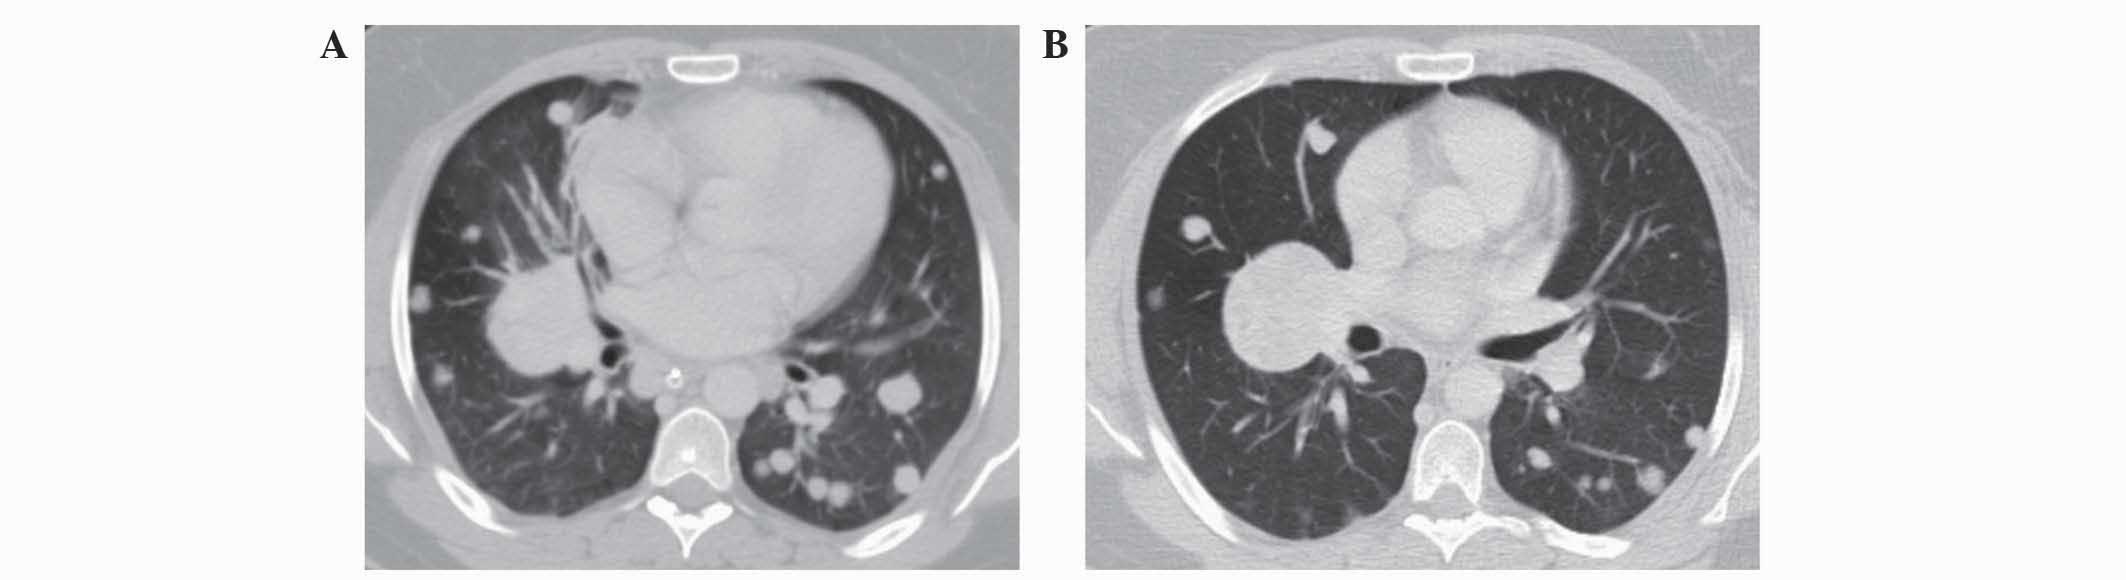

A CT scan for a systemic evaluation demonstrated multiple bilateral lung metastases (Fig. 3A), without evidence of brain or abdominal recurrence. In May 2012, the patient was administered with a mTOR inhibitor as a first-line treatment for metastatic disease (10 mg oral everolimus once daily). Following two months of treatment, improvement in the patient's lung metastases (Fig. 3B), quality of life and symptoms was observed. All symptoms of dyspnea, abdominal pain and weakness were improved, and the patient was able to stop using the wheelchair. Radiological evaluations revealed stable disease under continued treatment with everolimus that lasted for 18 months. During this period, the patient was asymptomatic and had an ECOG performance status of 0. The patient was followed up every two months, and follow-up appointments consisted of history and physical evaluation, cell blood count, blood biochemistry and CT.